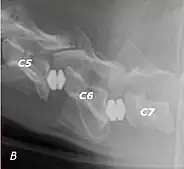

Wobbler disease is probably inherited in the Borzoi, Great Dane, Doberman, and Basset Hound.[2] Instability of the vertebrae of the neck (usually the caudal neck) causes spinal cord compression. In younger dogs such as Great Danes less than two years of age, wobbler disease is caused by stenosis (narrowing) of the vertebral canal[3] related to degeneration of the dorsal articular facets and subsequent thickening of the associated joint capsules and ligaments.[1] A high-protein diet may contribute to its development.[4] In middle-aged and older dogs such as Dobermans, intervertebral disc disease leads to bulging of the disc or herniation of the disc contents, and the spinal cord is compressed.[3] In Great Danes, the C4 to C6 vertebrae are most commonly affected; in Dobermans, the C5 to C7 vertebrae are affected.[5]

The disease tends to be gradually progressive. Symptoms such as weakness, ataxia, and dragging of the toes start in the rear legs. Dogs often have a crouching stance with a downward flexed neck. The disease progresses to the front legs, but the symptoms are less severe. Neck pain is sometimes seen. Symptoms are usually gradual in onset, but may progress rapidly following trauma.[6] X-rays may show misaligned vertebrae and narrow disk spaces, but it is not as effective as a myelogram, which reveals stenosis of the vertebral canal. Magnetic resonance imaging has been shown to be more effective at showing the location, nature, and severity of spinal cord compression than a myelogram.[7] Treatment is either medical to control the symptoms, usually with corticosteroids and cage rest, or surgical to correct the spinal cord compression. The prognosis is guarded in either case. Surgery may fully correct the problem, but it is technically difficult and relapses may occur. Types of surgery include ventral decompression of the spinal cord (ventral slot technique), dorsal decompression, and vertebral stabilization.[8] One study showed no significant advantage to any of the common spinal cord decompression procedures.[9] Another study showed that electroacupuncture may be a successful treatment for Wobbler disease.[10] A new surgical treatment using a proprietary medical device has been developed for dogs with disc-associated wobbler disease. It implants an artificial disc (cervical arthroplasty) in place of the affected disc space.[11]

Wobbler disease is definitively diagnosed by x-ray, nuclear scintigraphy or bone scan. X-rays will show channel widening or filling the easiest and are often most cost-effective to horse owners. X-rays will also show any structural anomaly, arthritis, facet remodeling, or bone spurs present. Preliminary diagnosis can be made by ultrasound but x-rays are needed to measure the true depth of facet involvement. For extent of damage to associated structures, veterinarians may opt to have the horse undergo a bone scan or nuclear scintigraphy.